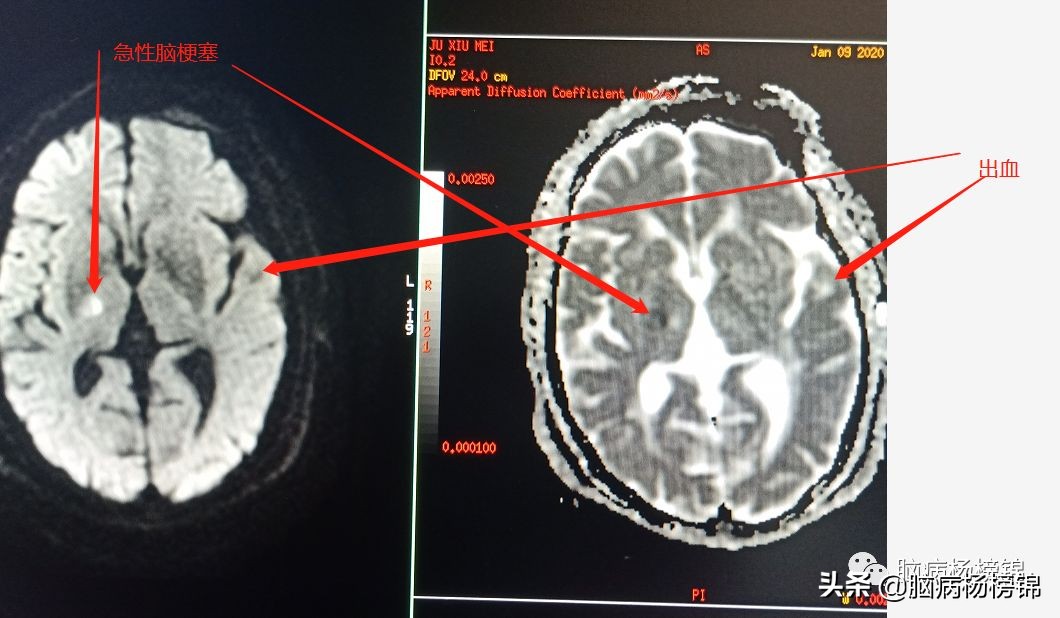

DWI显示:急性脑梗塞。

同时出现急性脑梗塞和脑出血,肯定不能溶栓。